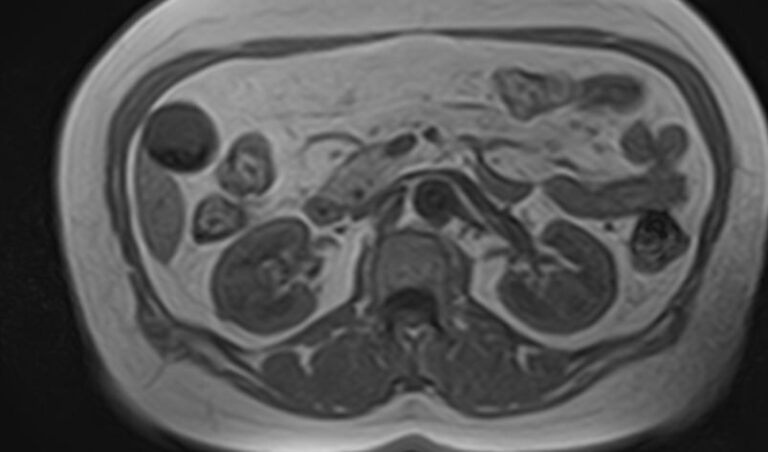

Мочеточники — это парные трубчатые органы, длиной приблизительно 25-30 см, соединяющие почечные лоханки с мочевым пузырем. Наиболее частой патологией является нарушение оттока мочи по мочеточнику за счет сужения (стриктуры) или обтурации (полной закупорки) его просвета.

Магнитно-резонансная томография позволяет получить информацию о состоянии мочеточников и окружающих мягких тканей для точной диагностики заболеваний данной анатомической области.

Что показывает МРТ мочеточников

В первую очередь необходимо отметить, что магнитно-резонансная томография мочеточников выполняется в комплексном обследовании почек и мочевыводящих путей, как самостоятельный метод диагностирования невозможен.

При помощи магнитно-резонансной томографии удается оценить состояние органов и выявить имеющиеся патологии: